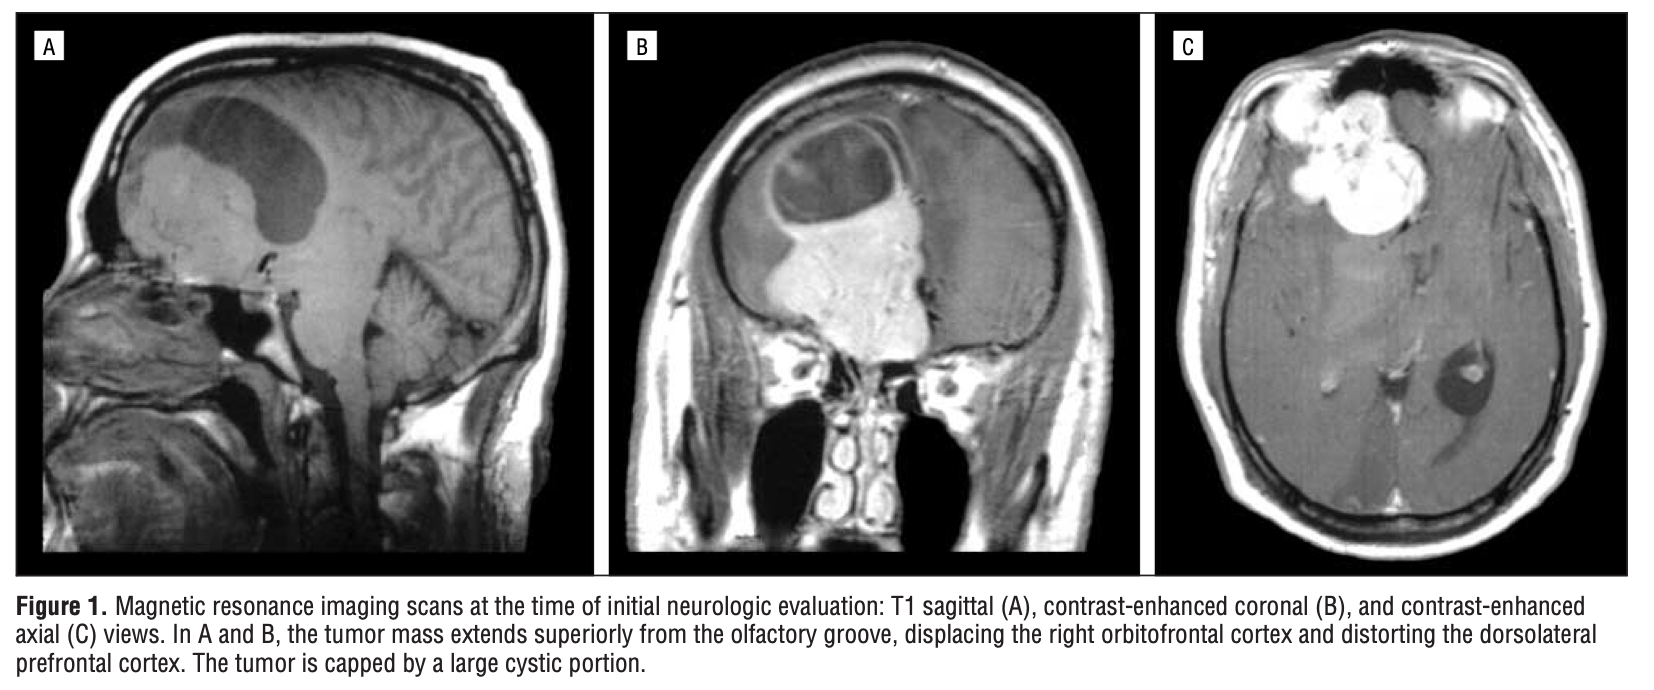

A investigação neurológica revelou a presença de um tumor no córtex orbitofrontal direito, região crítica para o controle de impulsos, avaliação social, atribuição de valor moral às ações e integração entre emoção e decisão. A ressonância magnética demonstrou uma lesão expansiva que comprometia diretamente circuitos orbitofrontais e suas conexões com estruturas límbicas relacionadas à emoção e ao desejo.

Meses depois, quando o tumor recidivou, os impulsos retornaram com as mesmas características: intrusivos, moralmente rejeitados pelo paciente, porém intensos a ponto de gerar risco para terceiros. Após nova intervenção neurocirúrgica e tratamento complementar, os sintomas desapareceram novamente, reforçando a relação direta entre o crescimento tumoral e os comportamentos. Essa oscilação temporal — presença dos impulsos com o tumor ativo, remissão completa após a cirurgia, e recorrência quando houve recrescimento tumoral — fornece uma evidência rara e contundente da dependência da vontade e do controle moral em relação a circuitos neurais orbitofrontais.